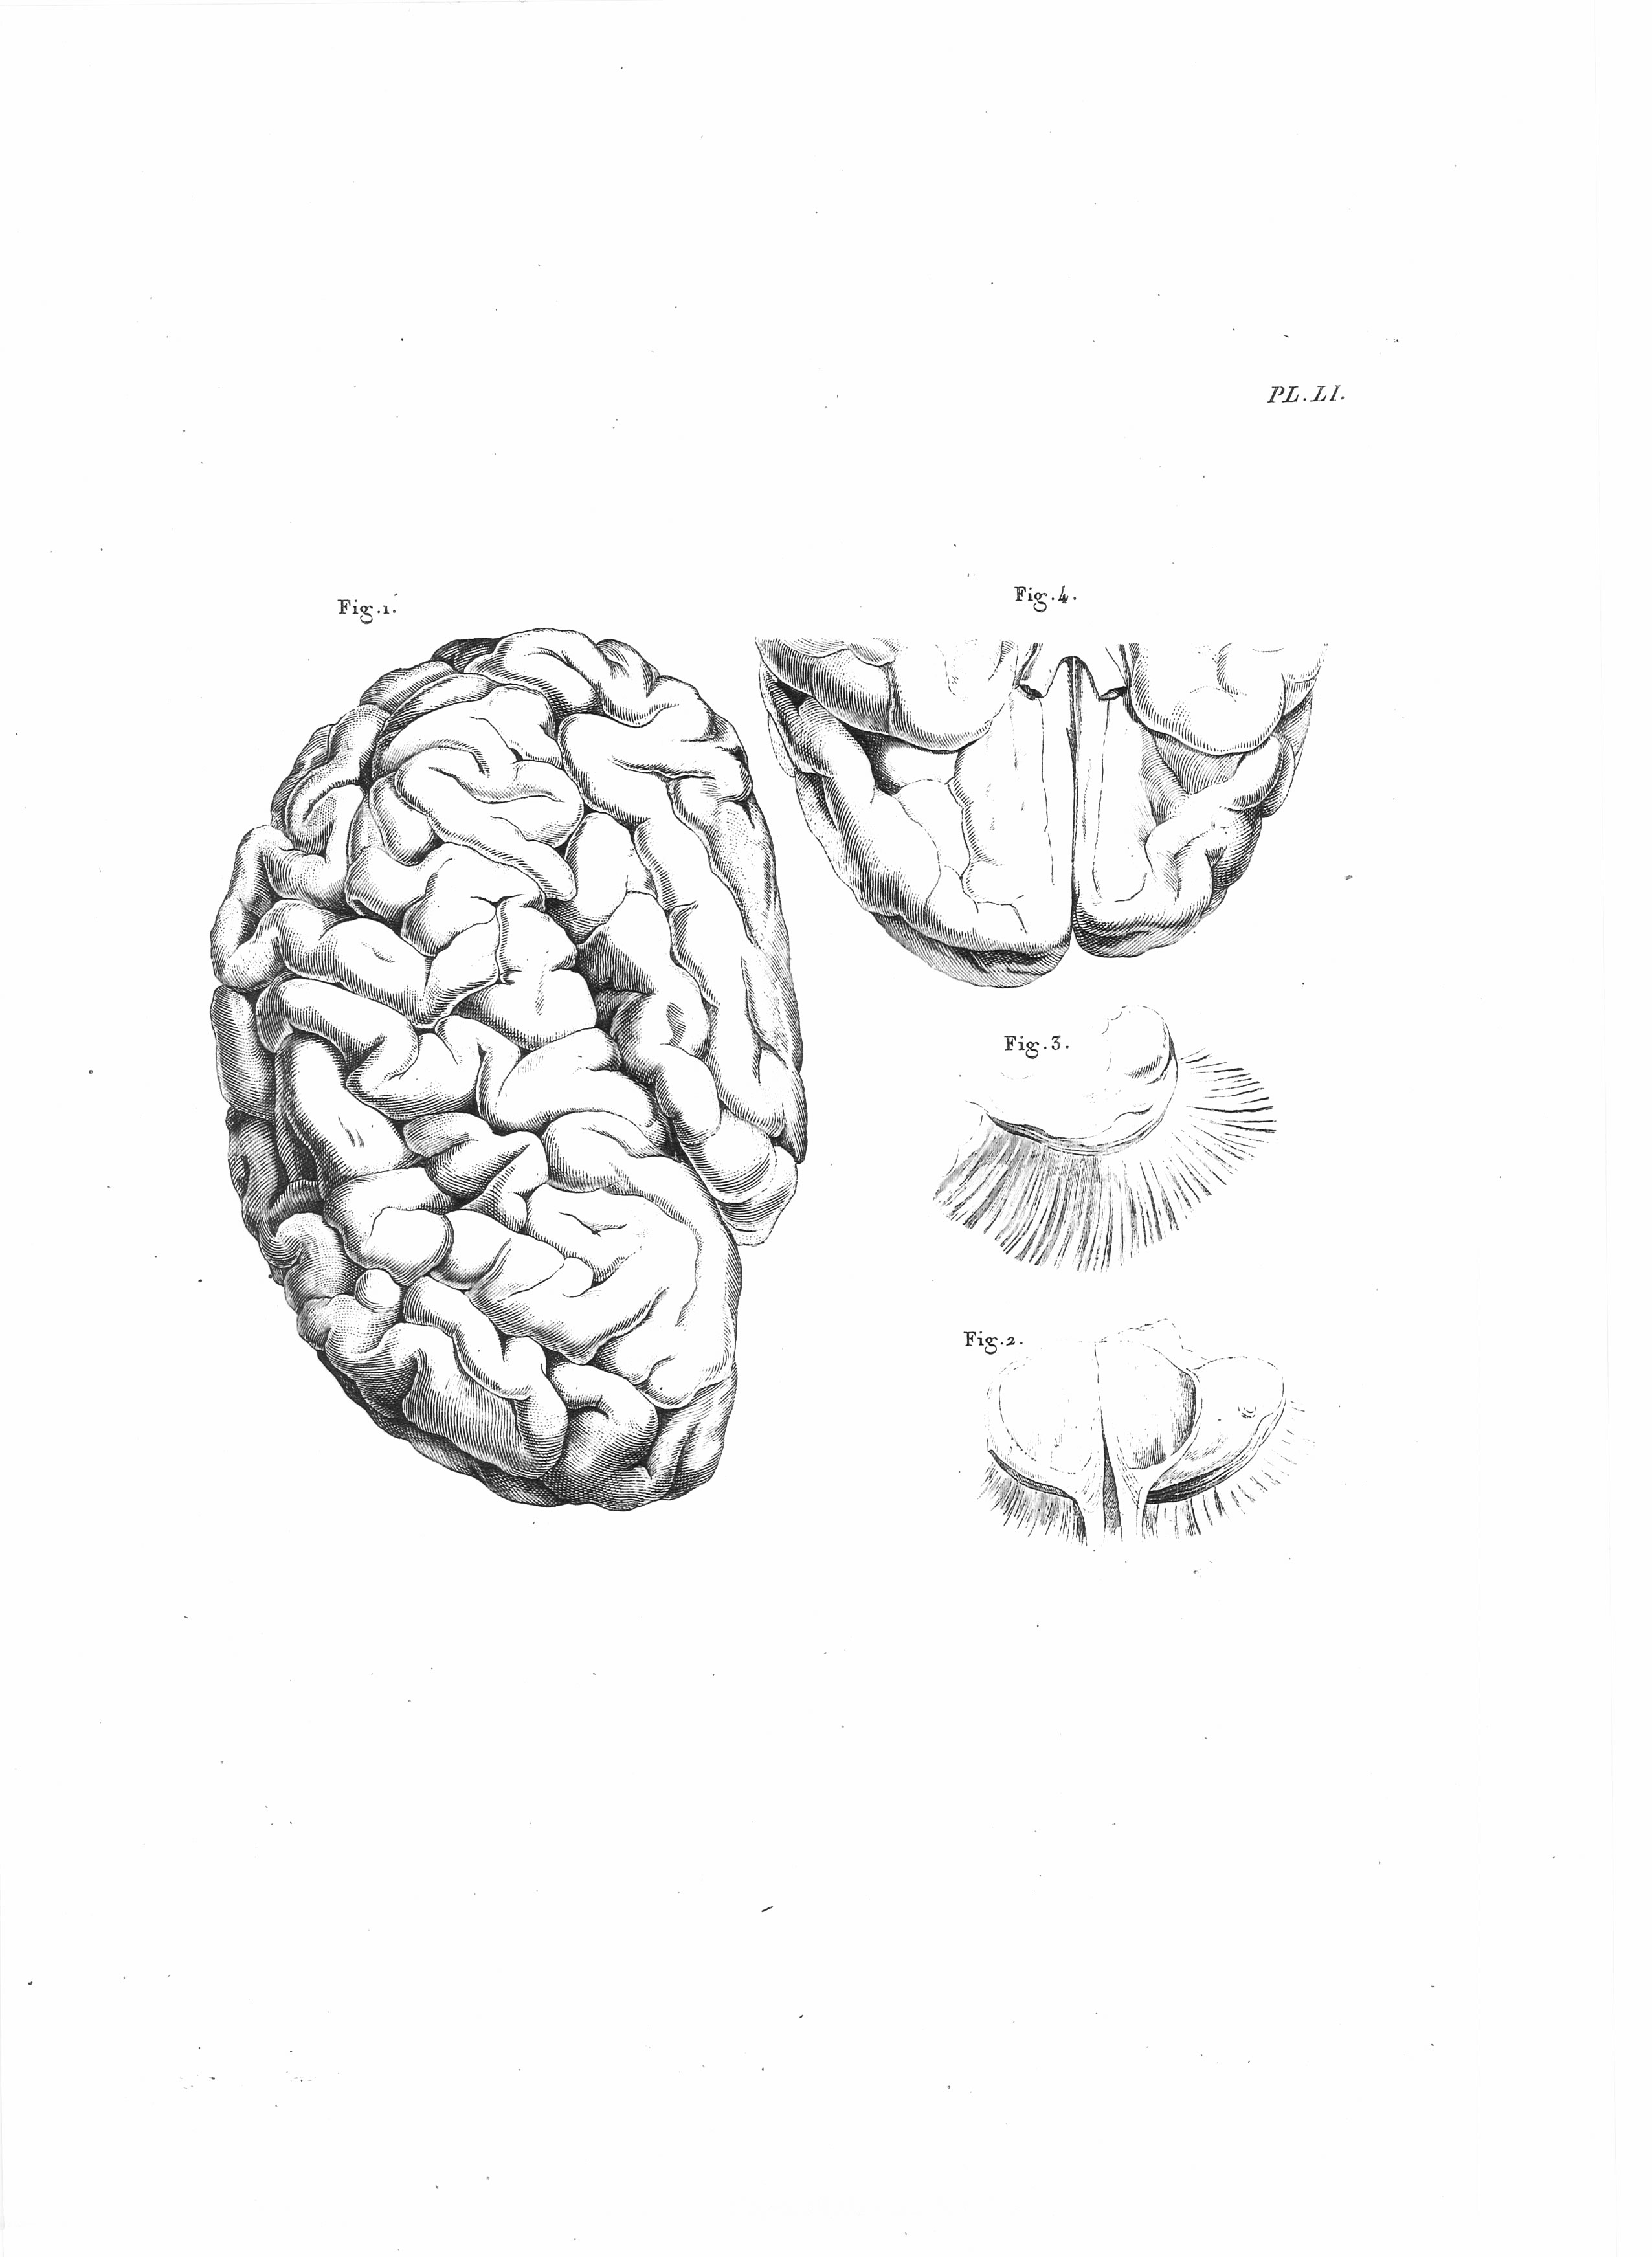

Gall, F. J. (1818). Anatomie et physiologie du système nerveux en général, et du cerveau en particulier, Avec des observations sur la possibilité de reconnoître plusieurs dispositions intellectuelles et morales de l´homme et des animaux, par la configuration de leurs têtes.

Librairie Grecque-Latine-Allemande, Vol. 3, I-XXXV u. 1-379 100 planches.